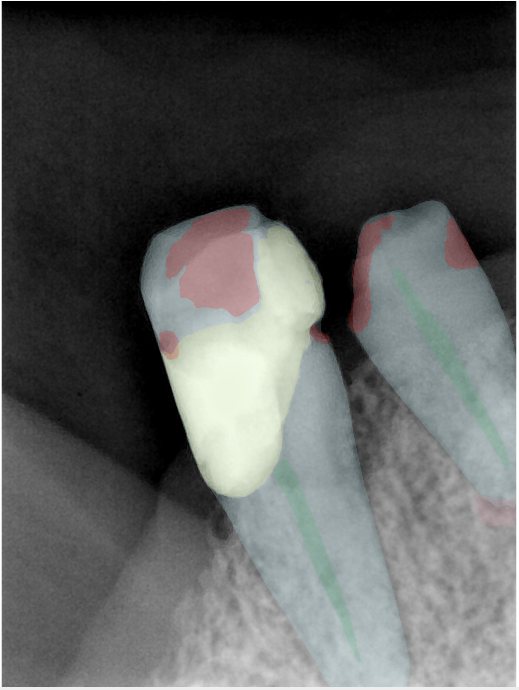

CR/DR 牙齿分割阶段记录

当前进展

- 完成了 CR/DR 牙齿相关分割训练

- 当前结果已经达到阶段预期,但仍有细节问题需要继续处理

相关测试

遇到的问题

- 训练过程中出现过 mask 下移问题

- 部分结果会出现 box 填充异常

- mask 边缘仍然有比较明显的锯齿感

参考

第二版算法问题测试